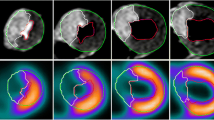

In two animals (=four sections), the septal segment of the left ventricular myocardium had to be excluded from the analysis because of beam-hardening artifacts caused by contrast material passage through the right ventricle. These artifacts resulted in hypo- and hyperdense streak artifacts averting any assessment of the affected myocardium. Thus, 36/40 myocardial segments (90%) were assessable. Visual assessment of MR imaging and MDCT revealed hypo-enhancement defined as myocardial ischemia in the identical 10/36 assessable segments. TTC staining proved the presence of myocardial infarction in these segments (Fig. 3). For MR imaging as well as for MDCT analysis of SImax, the Tmax and slope showed significant differences between normal and infarcted myocardium. For CAT, no significant differences were found. Furthermore, absolute values showed significant differences between MR imaging and MDCT results (P<0.001). Fig. 4 shows time-density/SI curves for MDCT and MR imaging. In detail, results for the semiquantitative analysis of the contrast enhancement are given in Table 1.

These results indicate that MDCT, despite its limitations, is promising for myocardial perfusion imaging. Moreover, hypo-enhancement was shown to be related directly to myocardial infarction when compared to TTC staining. On MDCT, however, hypo-enhanced regions were slightly larger than the areas of acute myocardial infarction detected by MR imaging or TTC staining. This finding is in agreement with the results reported from other study groups [5, 15] and might be explained by a reduced perfusion in combination with an edema in the peri-infarction zone [17]. As both mechanisms result in lower attenuation values when compared with healthy myocardium [18], these mechanisms are likely to contribute to the overestimation of the hypoperfused areas on MDCT. In our study the difference of the infarct size was less between MDCT and MR imaging when compared to the results reported by Nikolaou et al. [15]. This might be due to the different methods of data acquisition. Dynamic MDCT imaging may provide information that is more similar to MR perfusion imaging than arterial phase MDCT. Moreover, the difference between hypoperfused areas on MDCT and infarct size as determined from TTC staining was expected to be larger than actually was found. This finding might be due to the point of MDCT image reconstruction. According to our experience, the measured infarct size is considerably influenced by the point of image reconstruction.